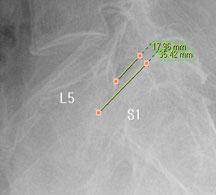

뼈가 앞으로 밀려나갔다고 하니 척추가 당장이라도 주저 앉을 것 같고, 한없이 밀려나갈 것 같지만 일반적으로 밀려나간 뼈는 대부분 1-2단계(25~50%) 정도 밀려나간 상태에서 안정화되는 경향을 보이기 때문에 그 자체로는 문제가 되지 않습니다.

즉, 척추전방위증은 통증을 일으키는 원인질환(디스크, 협착증)을 치료하는 것이 척추 뼈를 더 이상 앞으로 밀려나가지 않게 하는 치료라고 볼 수 있습니다. 모커리는 뼈가 50% 이상 밀려나간 2단계의 척추전방위증도 비수술로 치료하고 있으며, 이러한 한방치료 효과를 객관적으로 검증하여 유명학회 및 논문에 계속해서 발표하고 있습니다.

모커리한방병원은 2013년 1월부터 2014년 3월까지 척추전방위증으로 입원한 환자를 대상으로 치료 전•후를 비교분석한 결과, 복합척추치료 약 3주 후 환자가 느끼는 허리와 엉덩이 통증지수가 7.1에서 3.1로 줄었으며, 통증 없이 걸을 수 있는 거리 역시 193m에서 568m로 약 3배 가량 증가했습니다. 이번 연구결과를 계기로 50% 정도 밀려나간 2단계의 척추전방위증 환자들도 수술 없이 충분히 치료될 수 있다는 것이 객관적으로 검증되었습니다.

모커리한방병원은 50% 정도 밀려나간 2단계의 척추전방위증 환자를 대상으로 약 3주간의 입원집중치료를 실시한 결과, 입원 시보다 80% 이상 통증이 감소되어 치료되었습니다. 통증 없이 걷는 시간도 약 3배 정도 증가되어 단기간에 수술 없이 높은 치료효과가 나타났다는 것을 대한침구의학회에 발표하였습니다. 50% 정도 밀려나간 2단계의 중증 척추전방전위증 환자이면서 심한 척추협착증 증상을 나타내는 환자를 치료한 결과입니다.